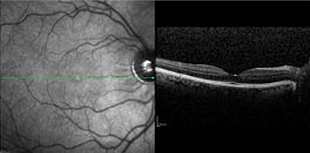

Το Μάιο του 2008 στο Πανελλήνιο Οφθαλμολογικό Συνέδριο που διοργανώθηκε στην Θεσσαλονίκη, η ομάδα του Athens Vision – οι Οφθαλμίατροι Γεώργιος Χαρώνης, Αναστάσιος Χαρώνης, Νικόλαος Ευαγγέλου, Αλέξανδρος Χαρώνης, Αλέξανδρος Μαναίος, Παντελής Ιωαννίδης και η οπτομέτρης Ευγενία Κωνσταντακοπούλου – παρουσίασε τα αποτελέσματα εργασιών με θέματα τη διαθλαστική χειρουργική, τη χειρουργική του καταρράκτη, τους ενδοφακούς προσθίου θαλάμου, τους πολυεστιακούς ενδοφακούς, τη μέτρηση της ενδοφθάλμιας πίεσης και της απεικόνισης της ωχράς κηλίδας. Ταυτόχρονα οι χειρουργοί-Οφθαλμίατροι του Athens Vision συμμετείχαν σε κλινικά φροντιστήρια για άλλους Οφθαλμιάτρους καλύπτοντας σχεδόν όλο το φάσμα των υπο-ειδικοτήτων της οφθαλμολογίας.